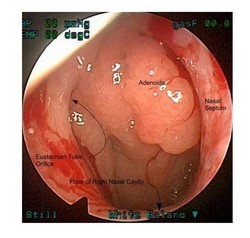

Увеличенные аденоиды.

Эндоскопическая картина

Для установления диагноза иногда бывает достаточно простого осмотра, но зачастую требуется «увидеть» аденоиды. Лучше всего непосредственно заглянуть в носоглотку с помощью эндоскопа.